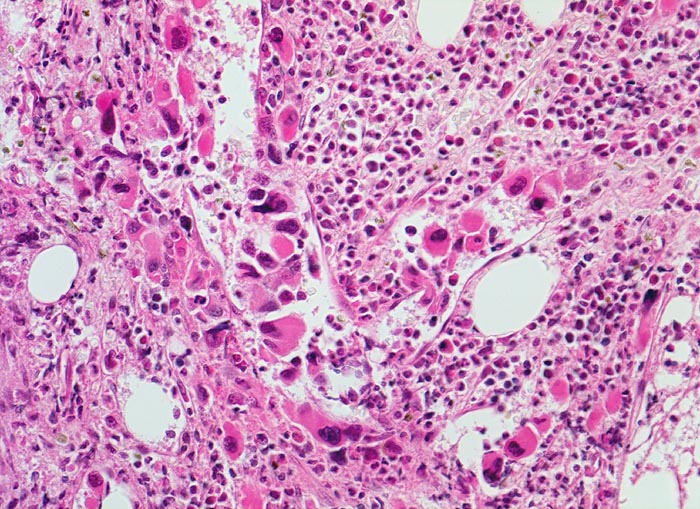

PathoPic – image database / PathoPic ID 3905 - Primäre Myelofibrose (PMF)

Primäre Myelofibrose (PMF)

Vermehrung von atypischen, in Gruppen liegenden Megakaryozyten mit hypolobierten Kernen. Teils nacktkernige Megakaryozyten (d.h. praktisch ohne Zytoplasma). Die Megakaryozyten liegen in einem dilatierten Sinusoid bzw. unmittelbar daneben. Hyperplasie von ausreifenden Granulozyten. Erythropoese hypoplastisch. Durch die Fibrose entsteht der Eindruck von strömenden Zellen (links im Bild).

Splenomegalie, leichte Anämie, Leukozytose und Thrombozytose festgestellt bei einer Routineuntersuchung bei abgesehen von leichter Müdigkeit asymptomatischer Patientin.